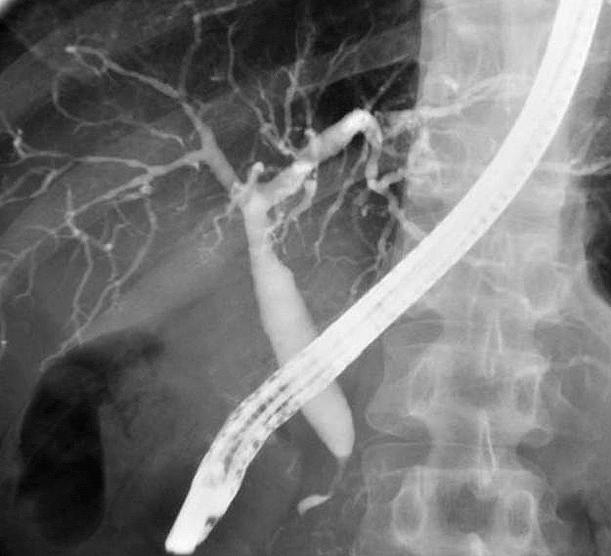

76歳の男性。黄疸を主訴に来院した。3日前に家族に皮膚の黄染を指摘されていた。3年前に唾液腺腫瘤を摘出した。飲酒は機会飲酒。意識は清明。身長168cm、体重57kg。体温36.4℃。呼吸数16/分。脈拍72/分、整。血圧126/82mmHg、眼球結膜に黄染を認める。心音と呼吸音とに異常を認めない。肝・牌を触知しない。尿所見:蛋白(-)、糖1+。血液所見:赤血球465万、Hb14.1g/dL、Ht45%、白血球8,100、血小板16万。血液生化学所見:血糖201mg/dL、HbA1c 6.7%(基準4.3〜5,8)、総蛋白9.6g/dL、アルブミン4.6g/dL、尿素室素19mg/dL、クレアチニン0.5mg/dL、総ピリルビン6.8mg/dL、AST86lU/L、ALT78IU/L、LD540IU/L(基準176〜353)、ALP1,230IU/L(基準115〜359)、Na138mEq/L、K4.OmEq/L、Cl102mEq/L。免疫学所見:CRP O.8mg/dL、抗核抗体 陽性、IgG 3,890mg/dL(基準739〜1,649)、IgA 118mg/dL(基準107〜363)、IgM 132mg/dL(基準46〜260)、CEA 2.8ng/mL(基準5以下)、CA19-9 26U/mL(基準37以下)。腹部造影CTと内視鏡的逆行性胆管膵管造影写真

検査では、軽度の肝機能障害、抗核抗体陽性、IgG高値あたり、画像では、膵臓がやたらでかい(CT)、胆管の先細り(ERCP)、膵管の狭小化・壁不正あたりが特徴らしい。私はこの疾患をよく知らないので適当なことを言ってるかもしれない。